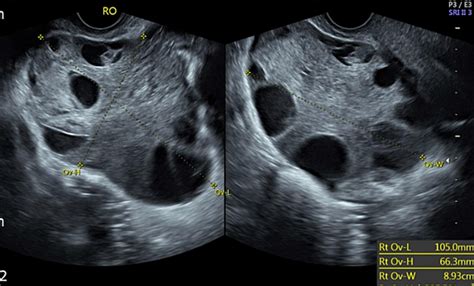

Enlargement of the Ovary

The most common finding is an increase in the size of the affected ovary. This occurs because the obstruction of the venous outflow—the veins responsible for carrying blood away from the ovary—leads to congestion, swelling, and edema. Often, the ovary will appear significantly larger than the unaffected contralateral ovary.

Peripheral Displacement of Follicles

In a healthy ovary, follicles are typically distributed throughout the ovarian tissue. When the ovary is enlarged due to edema caused by torsion, the follicles are often pushed to the periphery of the ovary, creating a “string of pearls” appearance. This is a classic sign often noted by ultrasound technicians and radiologists.